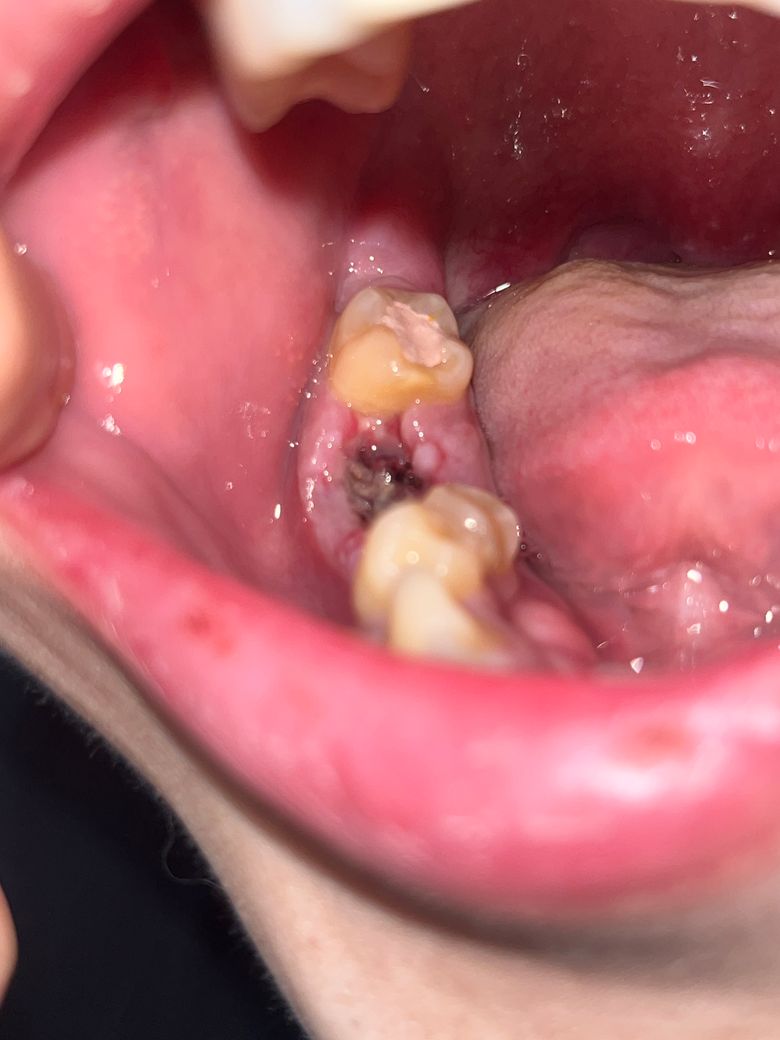

드라이소켓인가요? 한번봐주세용ㅠㅠ

며칠전 오른쪽 어금니 치아뿌리가 부러져 뽑았는데요 뽑는 과정은 엄청 힘들었습니다 오래걸렷고.. 치과선생님께서도 헤집으면서 뽑아서 아플거라고 하셨었습니다 3일차에 병원에 다시 들렀을땐 선생님께서는 별말 없으셨습니다

근데 현재 4~5일차인데 약간의 통증이 있으며 냄새도 좋지않고 턱과 볼이 뻐근합니다 드라이소켓인지궁금합니다

• 1번 째 사진

드라이소켓 가능성 보다는 정상적인 회복 과정일 가능성이 큽니다. 드라이소켓이라면 해당 부분의 통증이 약간이 아닌 극심하게 나타나게 됩니다. 현재 상태에서는 조금 더 지켜보는 것이 필요하며 발치 이후 지금과 같은 불편감은 자주 나타납니다.

사진상 드라이소켓으로 보이지는않으며, 발치후에 1-2주간은 통증 및 불편감이 나타날수 있습니다. 불편감이 있는 경우 소염진통제를 복용하고, 해당부위에 음식물 찌꺼기가 남지 않도록 가글을 하고, 소독용 헥사메딘 가글액 사용을 권합니다.

드라이소켓으로 보이지는 않습니다. 드라이소켓은 통증이 약간 나타나는 것이 아닌 참을 수 없는 통증이 생깁니다.

드라이소켓의 가능성은 있어보입니다 발치 후 주의사항 잘 지키시고 통증이 심하면 치과를 가보시기 바랍니다

드라이 소켓은 아닌거 같습니다. 상처가 심해서 그런거 같으니 치과에 가셔서 소독한번 받으시는게 좋을것같습니다.